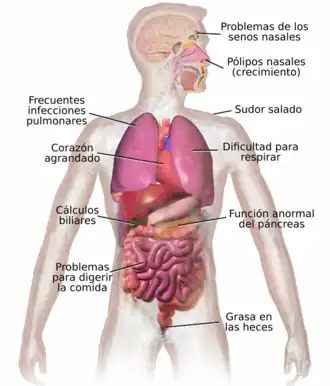

La fibrosis quística (abreviatura FQ) es una enfermedad genética de herencia autosómica recesiva que afecta principalmente a los pulmones, y en menor medida al páncreas, hígado e intestino, provocando la acumulación de moco espeso y pegajoso en estas zonas. Es uno de los tipos de enfermedad pulmonar crónica más común en niños y adultos jóvenes, y es un trastorno potencialmente mortal; los pacientes suelen fallecer por infecciones pulmonares debido a Pseudomonas o Staphylococcus.

La FQ afecta a múltiples órganos y sistemas, originando secreciones anómalas y espesas de las glándulas exocrinas. La principal causa de morbilidad y mortalidad es la afectación pulmonar, causante del 95 % de los fallecimientos, sobre todo por infecciones repetidas originadas por obstrucción bronquial debida a la secreción de mucosidad muy espesa. Otros órganos afectados son el páncreas y en ocasiones el testículo.[2][3] [4]

La sintomatología de la fibrosis quística varía en función de la edad del individuo, el grado en que se ven afectados órganos específicos, la terapéutica instituida previamente, y los tipos de infecciones asociadas. Esta enfermedad compromete al organismo en su totalidad y muestra su impacto sobre el crecimiento, la función respiratoria, la digestión. El periodo neonatal se caracteriza por un pobre aumento de peso y por obstrucción intestinal producida por heces densas y voluminosas. Otros síntomas aparecen, más tarde, durante la niñez y al inicio de la edad adulta. Estos incluyen retardo del crecimiento, advenimiento de la enfermedad pulmonar, y dificultades crecientes por la mala absorción de vitaminas y nutrientes en el tracto gastrointestinal.

A la mayoría de los niños se les diagnostica fibrosis quística antes del primer año de vida, cuando la mucosidad pegajosa que afecta pulmones y páncreas, comienza a mostrar su impacto. En el tracto respiratorio, esas secreciones sirven como caldo de cultivo para diversas bacterias responsables de infecciones crónicas, con deterioro progresivo y permanente del parénquima pulmonar. Conforme se agrava la condición respiratoria, los pacientes sufren hipertensión pulmonar. Por otra parte, en el páncreas, el moco obstruye el tránsito de las enzimas sintetizadas por la glándula e impide que lleguen hasta el intestino para digerir y absorber el alimento.

El moco en los senos paranasales es igualmente denso y pegajoso, y también puede causar oclusión de los orificios por donde los senos habitualmente drenan, lo cual hace que se acumulen secreciones que actúan como caldo de cultivo para los patógenos antes mencionados. En estos casos, se pueden presentar dolor facial, fiebre, secreción nasal profusa y cefaleas. En las personas con FQ, a menudo se observa crecimiento sobreabundante de tejido nasal (pólipos), a consecuencia de la inflamación por infección sinusal crónica. Estos pólipos pueden agravar la obstrucción de las vías respiratorias superiores e intensificar las dificultades respiratorias.[9][10]

El moco glutinoso observado en el pulmón tiene su correlato en las secreciones espesas del Páncreas, órgano responsable de proveer jugos digestivos que facilitan la descomposición química de los alimentos. Estas secreciones impiden el movimiento de las enzimas pancreáticas hacia el intestino y producen daño irreversible en el páncreas, a menudo acompañado de dolorosa inflamación (pancreatitis).[14] La deficiencia de enzimas digestivas se traduce en un impedimento para absorber los nutrientes, con la subsiguiente excreción de estos en las heces: este trastorno es conocido como malabsorción. La malabsorción conduce a la desnutrición y al retardo en el crecimiento y desarrollo, ambos debidos a la baja biodisponibilidad calórica. Las personas con FQ tienen, en particular, problemas para absorber las vitaminas A, D, E, y K. Además de la afección pancreática, suelen experimentar acidez crónica, xerostomía, obstrucción intestinal por intususcepción, y constipación.[15] Los pacientes mayores desarrollan también el síndrome de obstrucción intestinal distal causado por las heces glutinosas.[16]

Estas secreciones también pueden causar problemas en el hígado. La bilis, producida por esta víscera para facilitar la digestión, podría bloquear las vías biliares, dañando los tejidos adyacentes. Con el tiempo, esta situación conduce a la cirrosis. En ese caso, resultan comprometidas funciones de primer orden, tales como las implicadas en la neutralización de toxinas, y en la síntesis de importantes proteínas (por ejemplo, los factores de coagulación, responsables de la coagulación sanguínea).[17]

El páncreas contiene los islotes de Langerhans, que son los responsables de producir insulina, una hormona que ayuda a regular los niveles de glucosa en sangre. Un daño en el páncreas puede provocar la pérdida de las células de los islotes y conducir a la diabetes.[18] Por otra parte, la vitamina D suplementada por la alimentación está implicada en la regulación del calcio y del fósforo. La baja disponibilidad de esta, a causa de la mala absorción, conduce a la osteoporosis, aumentando el riesgo de sufrir fracturas.[19] Adicionalmente, las personas con FQ a menudo presentan, en manos y pies, una malformación denominada dedos en palillo de tambor, la cual se debe a los efectos de esta enfermedad crónica y a la hipoxia en sus huesos.